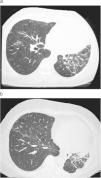

Paciente varón de 35 años de edad, que 5 años atrás había ingresado para estudio de hemiatrofia corporal y trastorno cutáneo izquierdo. En ese momento sólo refería debilidad muscular del lado izquierdo y se encontraba asintomático desde el punto de vista respiratorio. Durante la exploración física se observó leve atrofia de la musculatura de la hemicara y hemilengua izquierdas, así como pérdida del vello en el hemitórax izquierdo y telangiectasias, lesión lineal frontal izquierda que parecía afectar la piel y el tejido subcutáneo, además de importante atrofia muscular de predominio en la zona distal inferior izquierda. En las pruebas analíticas efectuadas sólo destacaron unos títulos de anticuerpos antinucleares de 1/320, C3 de 90mg/dl y C4 de 15mg/dl; los anticuerpos contra antígenos nucleares extraíbles, anti-Ro, anti-La, anti-Sm, ScL-70, anti-Jo1, anti-PM1, citoplásmicos antineutrófilos, antimitocondriales y anticentrómero fueron negativos, y la función renal y hepática, normal. El resto de pruebas complementarias efectuadas (radiografía de tórax y pruebas de función respiratoria) mostraron normalidad. Con todos estos datos, se llegó al diagnóstico de esclerosis localizada tipo morfea en coup de sabre. Un año y medio más tarde, se envió al paciente al Servicio de Neumología por disnea de esfuerzo y anormalidades en la radiografía de tórax, consistentes en pérdida de volumen en el hemitórax izquierdo con afectación intersticial homolateral reticular de tractos gruesos. Se le efectuó una tomografía computarizada de alta resolución, donde se confirmó la existencia de un infiltrado intersticial en el hemitórax izquierdo (figura 1a); el resto del parénquima era normal. Se le realizaron pruebas de función respiratoria, que demostraron una restricción leve-moderada, con una capacidad vital forzada (FVC) de 3.030ml (68%), volumen espiratorio forzado en el primer segundo (FEV1) de 2.550ml (67%), FEV1/FVC del 83% y capacidad pulmonar total de 4.190ml (66%). En la prueba de la marcha de 6min recorrió una distancia de 542m y alcanzó una saturación de oxígeno mínima del 95%. Al cabo de un año, el paciente manifestó mayor grado de disnea. La radiografía de tórax evidenció mayor pérdida de volumen en el hemitórax izquierdo, y la tomografía computarizada de alta resolución, una progresión importante del patrón intersticial (figura 1b), que se corroboró en las pruebas de función respiratoria, donde la FVC fue de 2.430ml (55%), el FEV1 de 1.800ml (48%), FEV1/FVC del 74% y capacidad pulmonar total de 3.010ml (48%). En la prueba de la marcha de 6min recorrió 500m y alcanzó una saturación de oxígeno mínima del 87%. Tras haber comprobado la progresión de la enfermedad pulmonar se decidió aumentar la dosis de esteroides y comenzar con azatioprina, tras lo cual se observó la estabilización de la afectación pulmonar.

Figura 1. a: leve afectación intersticial en el hemitórax izquierdo. b: progresión de la enfermedad al cabo de un año.